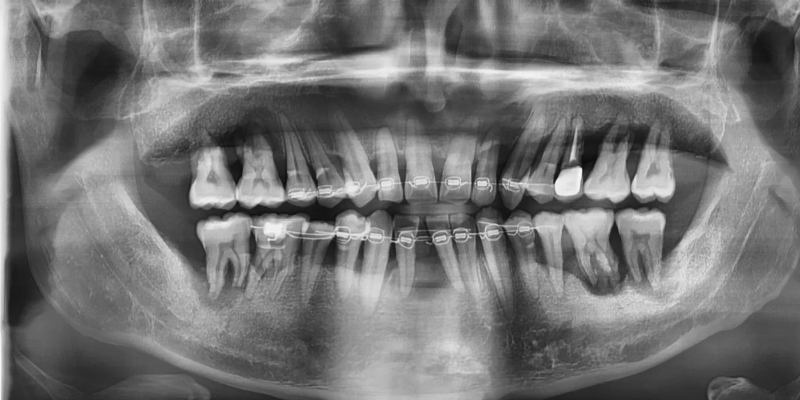

먼저 치아 교정을 통해

전치부 치아 배열을 정리하는

것부터 시작하였습니다.

그러나 앞니중에서도 치주가 너무 좋지않아

몹시 흔들리고 지지도 되지 않는

아래의 첫번째 앞니는 발치를 진행하였습니다.

전치부의 배열을 진행하면서

치조골의 파괴가 심각한 어금니 3개를 발치하고

임플란트를 식립하였습니다.